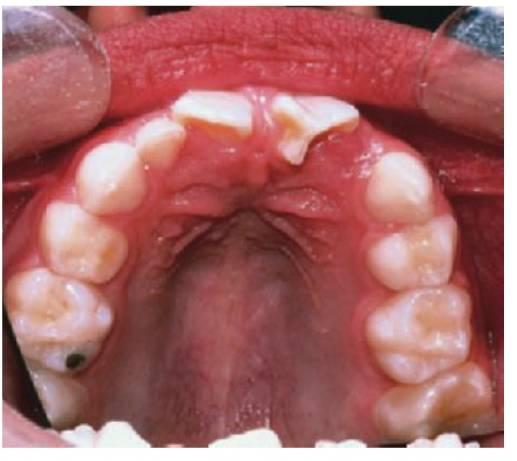

Los dientes supernumerarios surgen como resultado de una geminación de la lámina dental que se produce de forma esporádica o se heredan, como sucede con la displasia cleidocraneal (fig. 9.8).

La forma de los dientes puede recordar a la forma de las piezas normales (diente suplementario), es decir, incisiforme, caniniforme o molariforme; de no ser así, sería cónico o tuberculado.

Habitualmente se presenta como consecuencia del fallo en la erupción de uno o más dientes permanentes y en general presenta formas cónicas o tuberculadas.

- Erupción fallida o ectópica de un diente permanente (fig. 9.8B).

- A menudo erupcionan dientes cónicos que se pueden extraer con mucha facilidad (fig. 9.8A).

- Los dientes tuberculados o cónicos invertidos requieren extracción quirúrgica (fig. 9.8D) tan pronto como sea posible para permitir la erupción sin obstáculos del diente permanente.

- Resulta esencial localizar la posición del diente que debe extraerse antes de la cirugía. Pueden realizarse radiografías periapicales que emplean la técnica del desplazamiento del tubo (tube-shift) para localizar el diente, pero siempre entrañan la posibilidad de errores e interpretaciones erróneas. De la misma manera, pueden utilizarse radiografías panorámicas y oclusales maxilares estándar. La proyección oclusal de vértice permite obtener una muestra más precisa de la localización horizontal y anteroposterior, por lo que es la preferida (fig. 9.8C) para ayudar a determinar el procedimiento quirúrgico óptimo. Algunos centros prefieren no utilizar esta vía debido a una excesiva radiación en el cráneo.